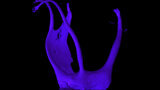

Clinical management of maxillary second molar root canal therapy in different anatomical situations